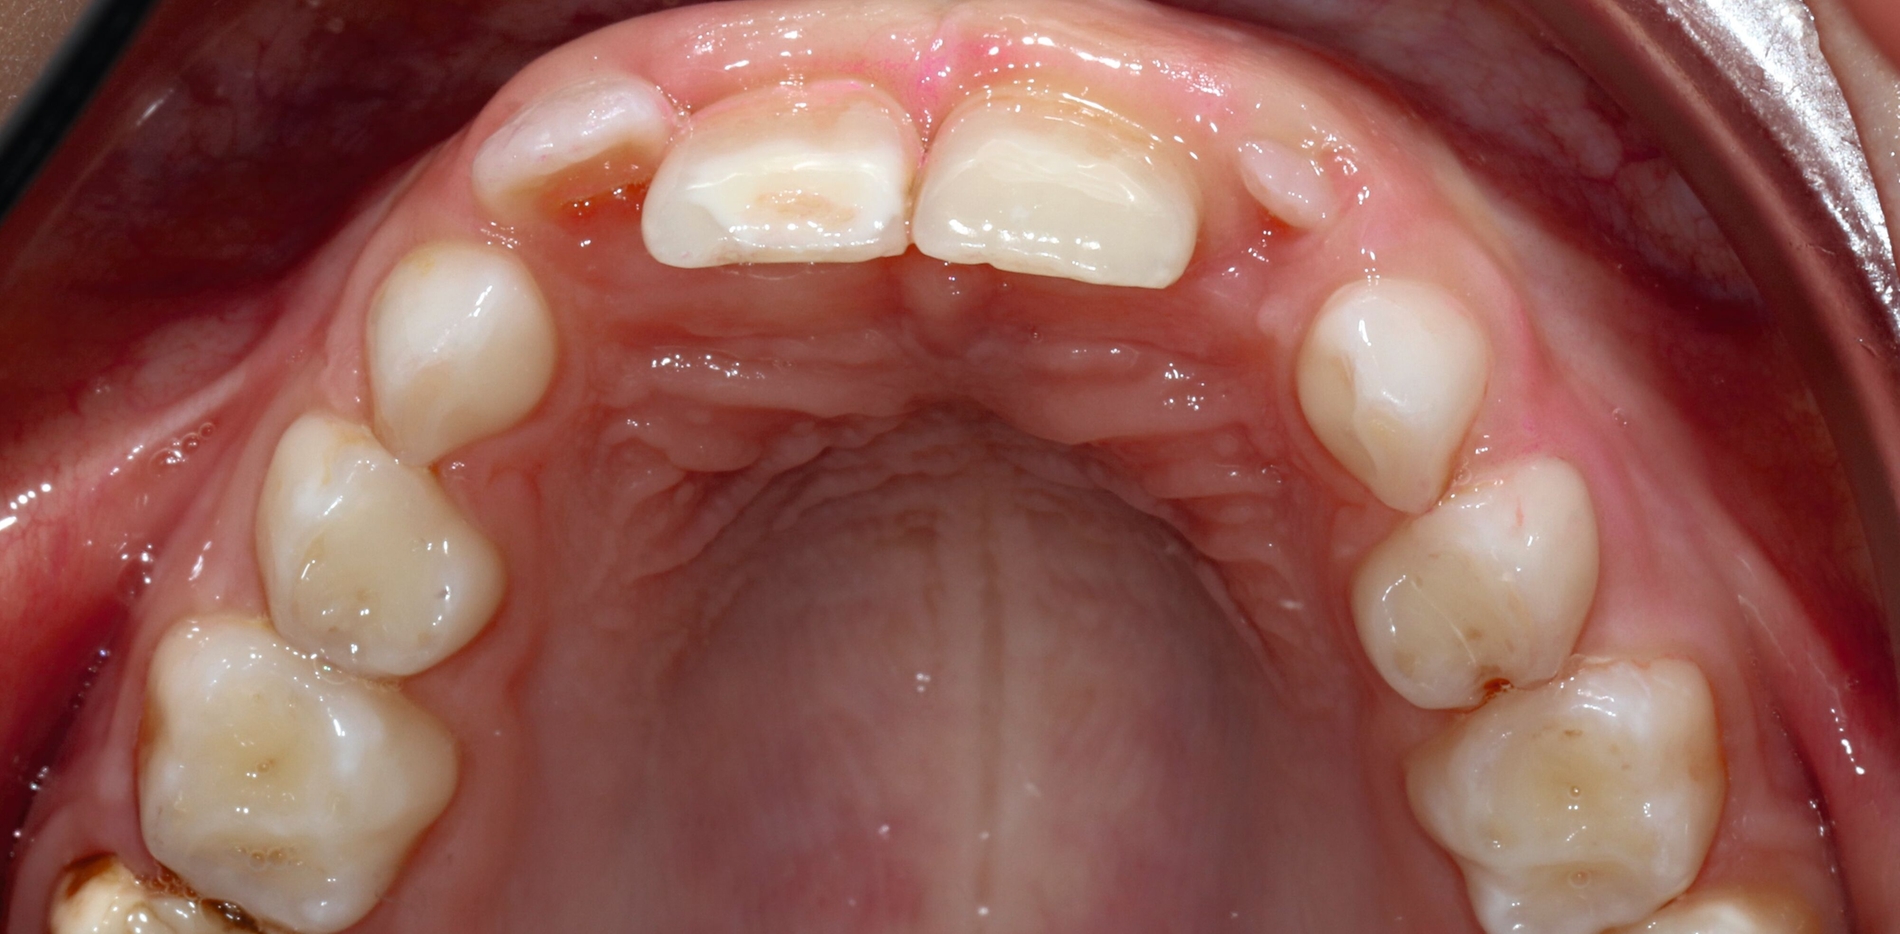

PD Dr. Ruth Santamaría Sanchez (Greifswald) stellte das Greifswalder Kariesmanagementkonzept vor,das die ganze Bandbreite von der Prävention über minimalinvasive Maßnahmen bis hin zur Restauration nach dem aktuellen Stand der Wissenschaft umfasst. Dabei werden klassische Prävention, Kariesinaktivierung (beispielsweise mit Silberfluorid oder Slicing), non- beziehungsweise minimalinvasive Verfahren wie die Hall-Technik sowie klassische Restaurationen und Lückenhalter beziehungsweise Platzmanagement miteinander verzahnt.